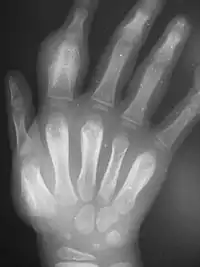

An irregularly-thickened first finger; proximal fingerbone is asymmetrically swollen

Dactylitis of secondary yaws due to periostitis

radiograph showing same hand with thickened bones

Periostitis of secondary yaws may be visible on an X-ray, even if not otherwise visible[2]